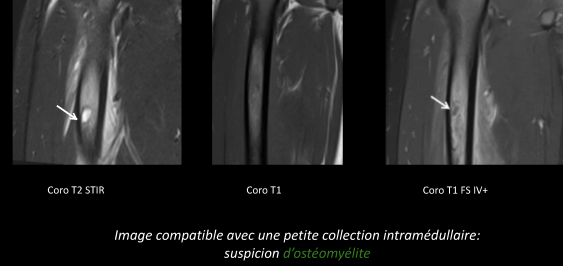

- Crises vaso-occlusives (Infarctus osseux, souvent multiples, l’hypersignal T1 spontané est spécifique pour le DD avec ostéomyélite)

- Ostéomyélites (DD de l’infarctus, pas évident, a suspecter si il ya des abcès, collections)